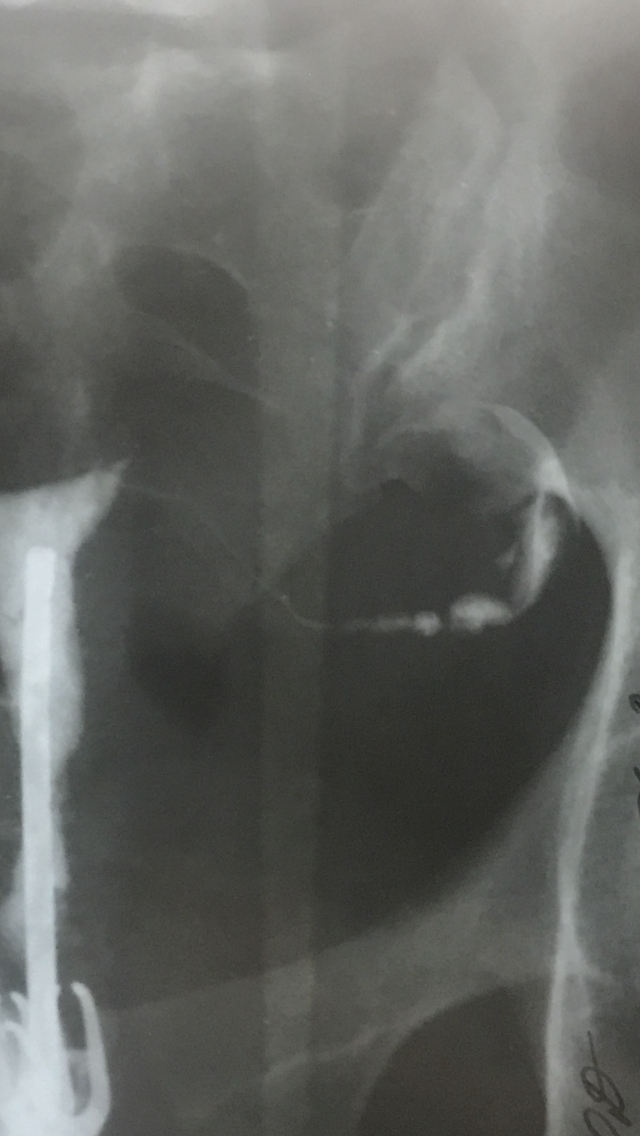

4. Гистеросальпингография. Этот пункт применим скорее для других заболеваний в этой рубрике, либо же в рамках обследования при жалобах на бесплодие